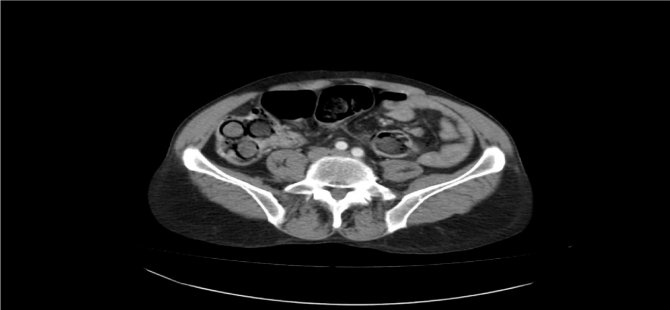

Polis, şahsın midesinde eroin olabileceğinden şüphelenip hemen hastanenin gastroenteroloji bölümüne götürdü. Burada tomografisi çekilen midede, sosis büyüklüğünde paketler tespit edildi. Ancak polis, emin olmak için daha sonra şahsa endoskopi işlemi de yaptırdı. Bu sayede ucunda ışıklı küçük bir kamera bulunan ve endoskopi adı verilen bir cihaz yardımıyla şahsın yemek borusu, mide, onikiparmak bağırsağı ve kalın bağırsaklarında 49 paket sosis büyüklüğünde paketler olduğu kesinleşti.